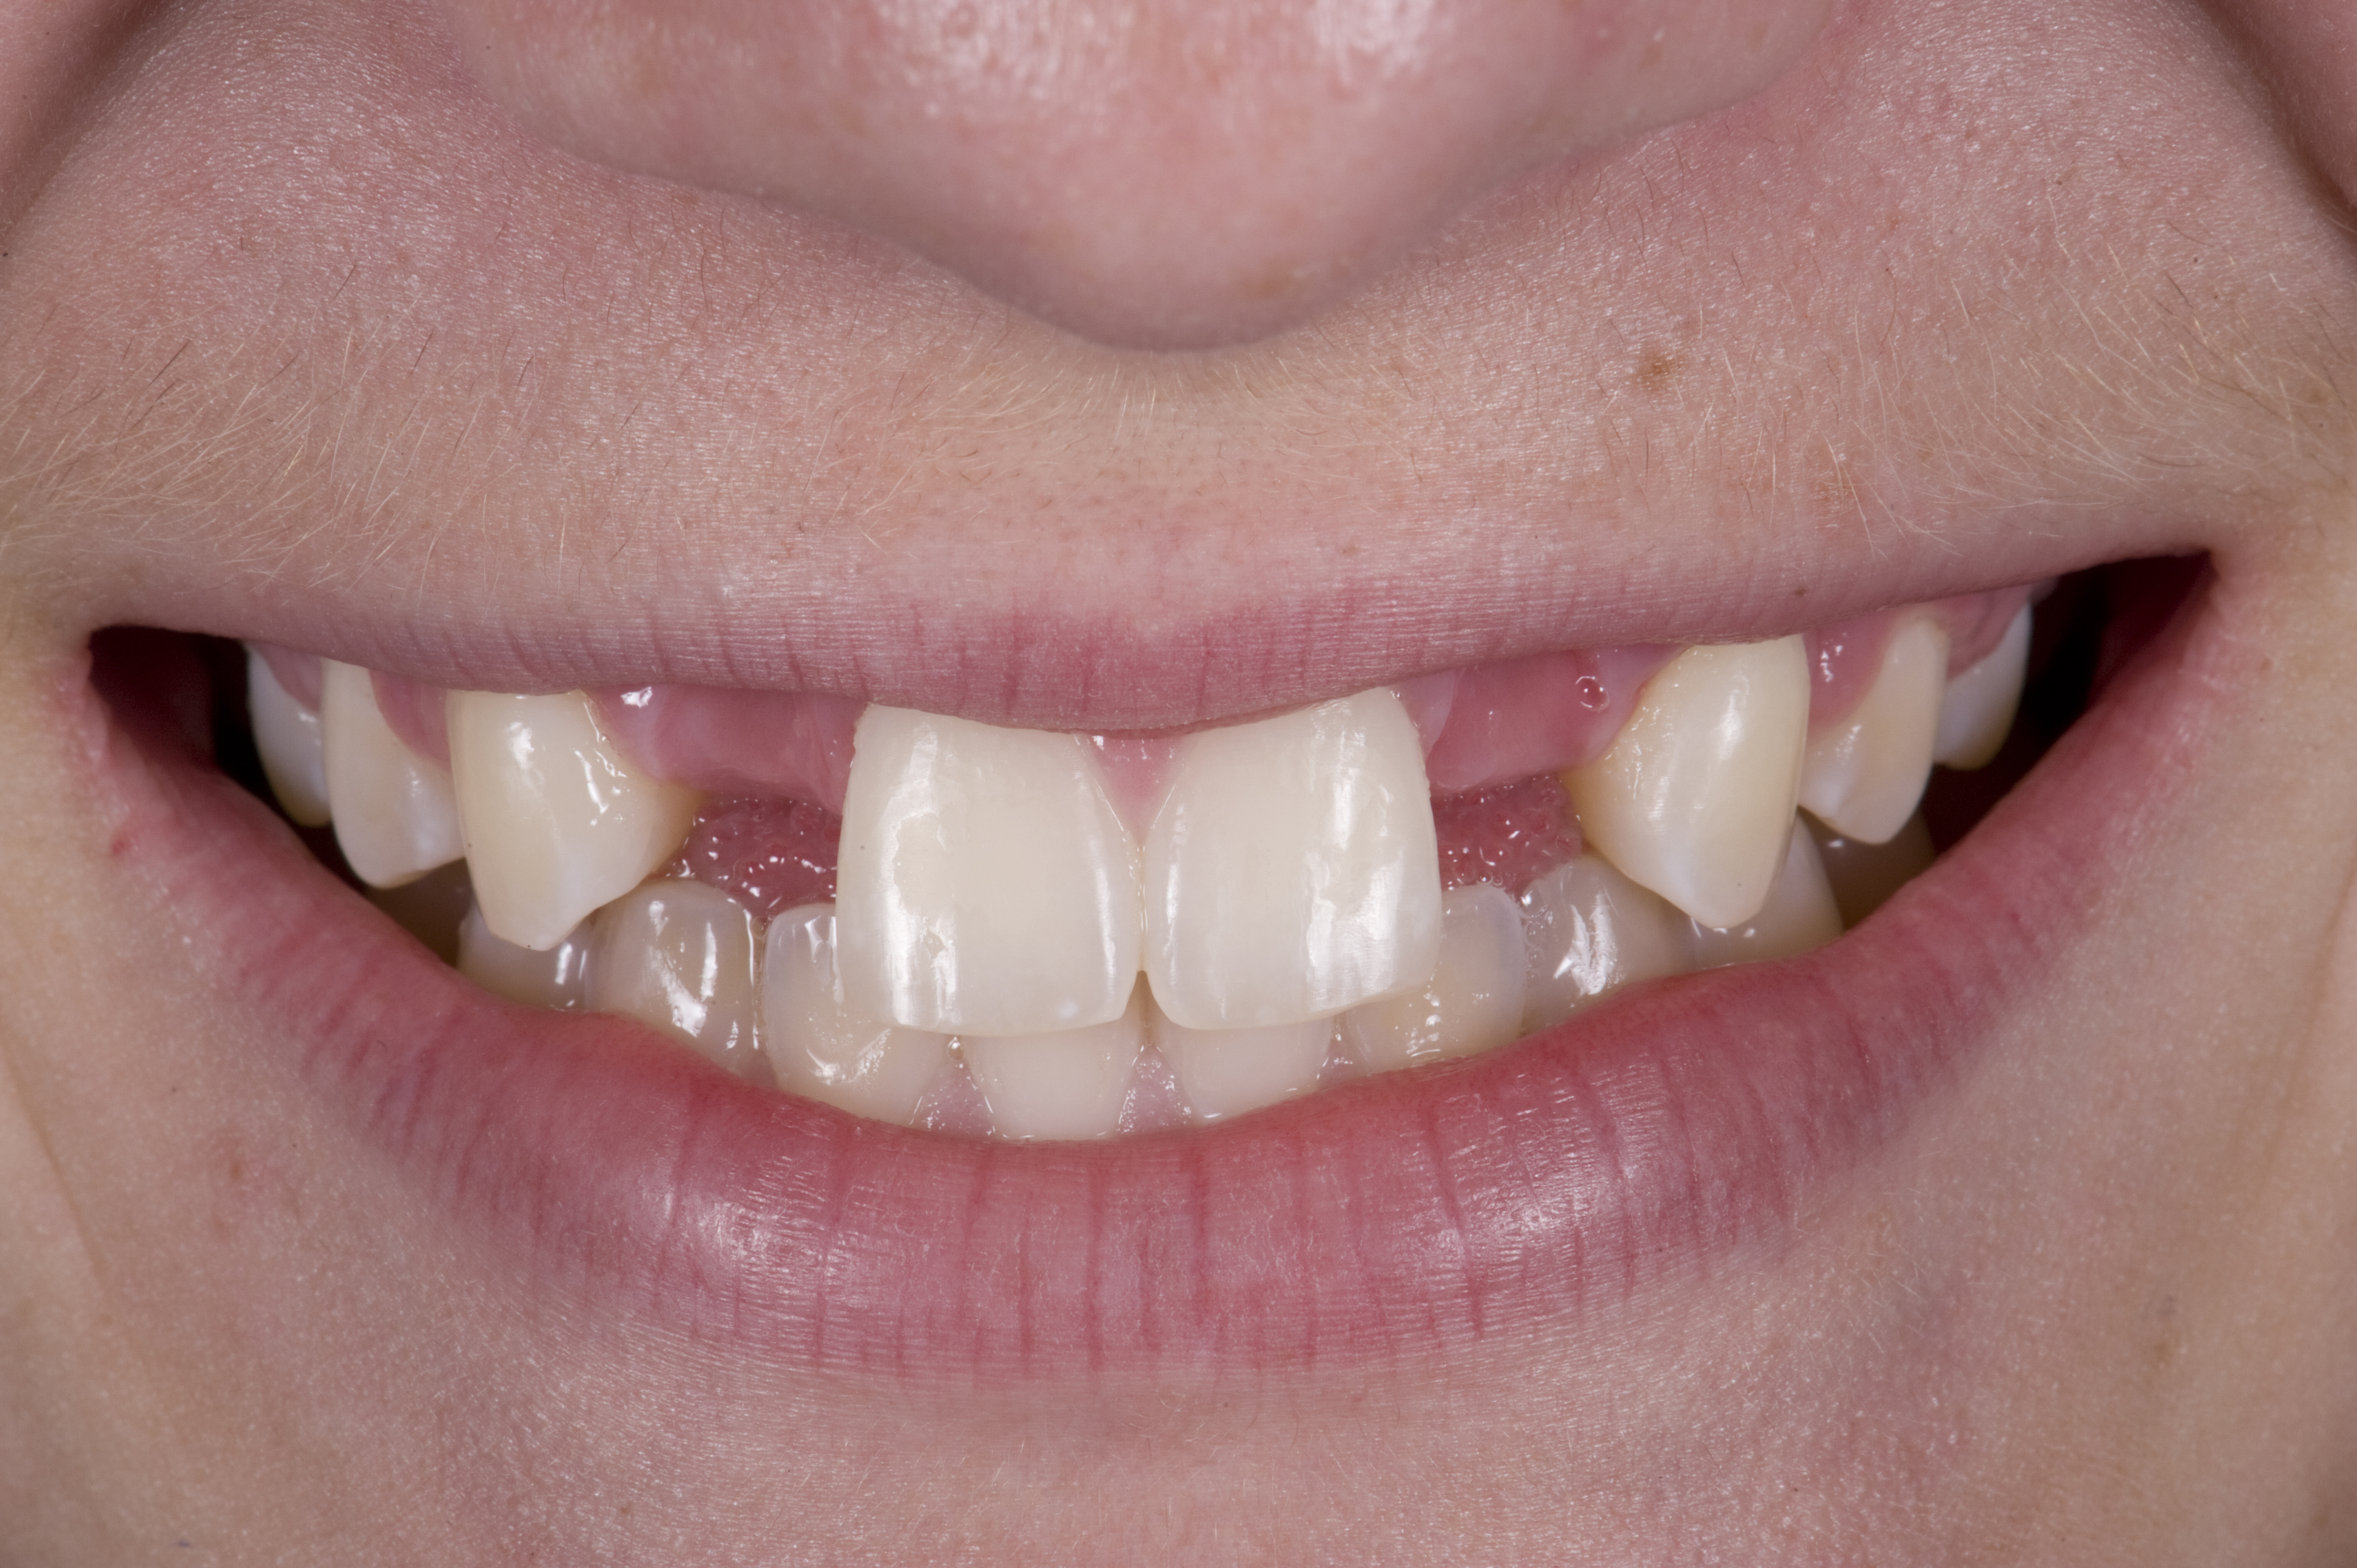

(13.) Deficient ridges in the areas of the missing lateral incisors.

Figure 13